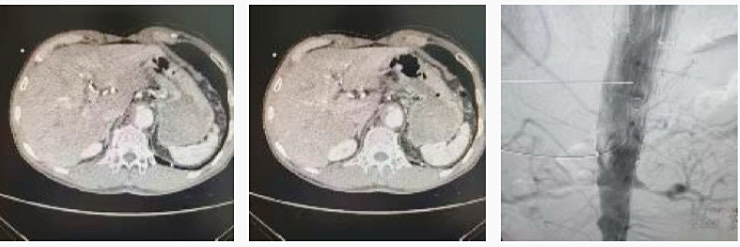

一名腹主动脉穿透溃疡并壁间血肿患者因急性胸腹痛入院,入院后胸心血管外科团队在黄小龙主任的带领下行腹腔干开窗点式隔绝,精准定位,不仅能为患者节省费用,手术达到良好效果,术后患者病情稳定,一周后患者康复出院。

胸心血管外科以“敬业福”换患者“健康福”。除夕前有两名患者在家时出现胸闷气促、呼吸困难、右下肢酸胀的症状,立即到我院就诊,胸心血管外科团队立即进行检查,定制手术方案,高质量完成2台肺栓塞取栓手术,收获患者满满好评。

一名九十五岁高龄患者因双下肢间歇性跛行入住胸心血管外科,经CTA检查显示双股浅动脉血管严重钙化、闭塞,胸心血管外科团队成功为高龄患者行下肢动脉溶栓吸栓术,术后造影显示动脉通畅良好。

一名63岁男性因右下肢发凉伴疼痛入住胸心血管外科,经完善检查后明确诊断为下肢动脉硬化闭塞症,胸心血管外科团队为患者行下肢动脉造影,经导管取栓术,取栓导管取出大量陈旧性血栓,复查造影腘动脉、胫腓干、胫前、胫后动脉及腓动脉通畅,患者下肢症状得到改善,立竿见影地解除了患者的病痛。